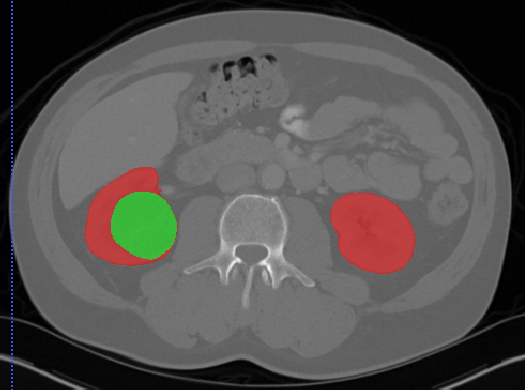

Edge-Aware 3D Image Segmentation Networks

[91]: Automated segmentation of kidneys and kidney tumors is an important step in quantifying the tumor’s morphometrical details to monitor the progression of the disease and accurately compare decisions regarding the kidney tumor treatment. Manual delineation techniques are often tedious, error-prone and require expert knowledge for creating unambiguous representation of kidneys and kidney tumors segmentation. We propose a 3D end-to-end edge-aware FCN for reliable kidney and kidney tumor semantic segmentation from arterial phase abdominal 3D CT scans. Our segmentation network consists of an encoder-decoder architecture that specifically accounts for organ and tumor semantics. We evaluate our model on the 2019 MICCAI KiTS Kidney Tumor Segmentation Challenge dataset. -

Furthermore, we extend our methodology and propose 3D boundary-aware FCNs for end-to-end and reliable semantic segmentation of kidneys and kidney tumor by encoding the information of edges in a dedicated stream that is supervised by edge-aware losses.

As is illustrated in Figure 2, our network consists of the main segmentation branch and the additional boundary stream that processes the feature maps at the boundary level. The main branch, following [90], is an asymmetric encoder-decoder structure. The input to the encoder is a crop which is initially fed into a convolution with 16 filters. Feature maps are then extracted at each resolution by feeding them into a residual block followed by a strided convolution (for downsizing and doubling of the feature dimension).

The bottom of the encoder entails four consecutive residual blocks that are connected to the decoder. The extracted feature maps in the decoder are upsampled using bilinear interpolation and added with feature maps from the encoder. The output of the decoder is concatenated with the output of the boundary and fed into a convolution with 2 channels where channel-wise sigmoid activation determines the probability of each voxel belonging to kidneys and tumor or only tumor classes.